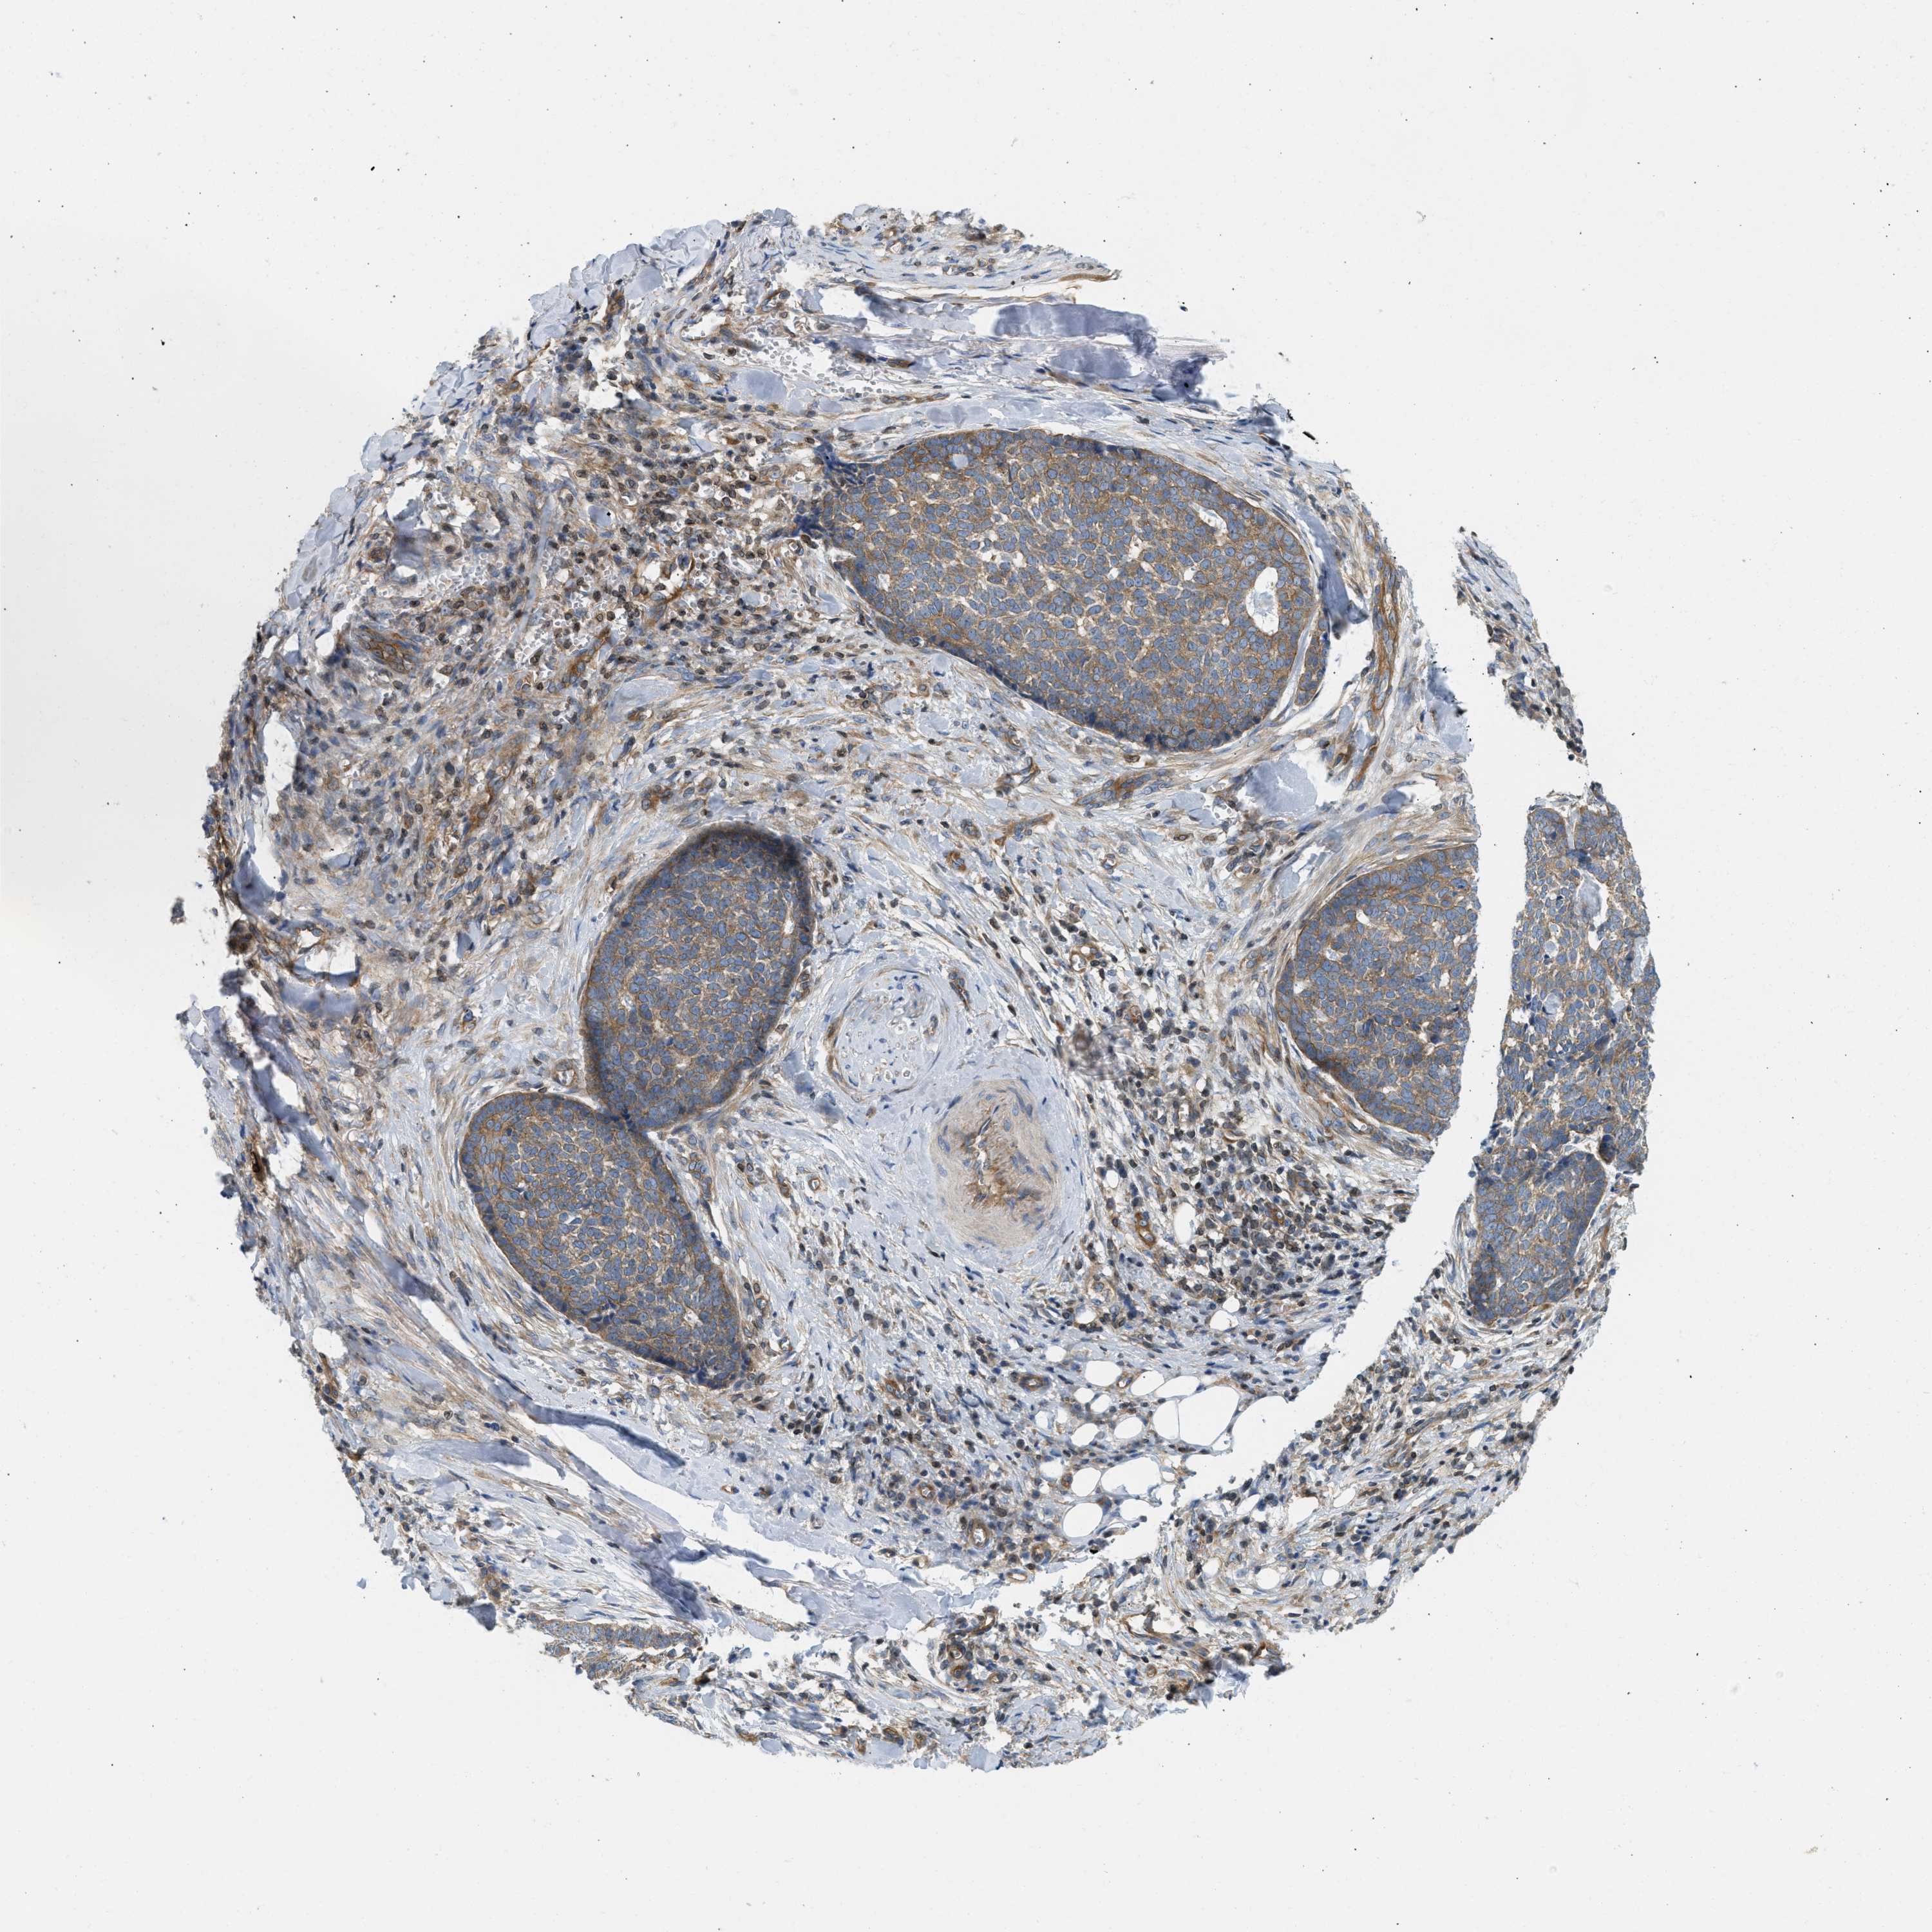

SKIN CANCER - Protein expressioni

A mouse-over function shows sample information and annotation data. Click on an image to view it in a full screen mode. Samples can be filtered based on level of antibody staining by selecting one or several of the following categories: high, medium, low and not detected. The assay and annotation is described here.

Antibody stainingi

Antibody staining in the annotated cell types in the current human tissue is reported as not detected, low, medium, or high, based on conventional immunohistochemistry profiling in selected tissues. This score is based on the combination of the staining intensity and fraction of stained cells.

Each image is clickable and will lead to virtual microscopy that enables deeper exploration of all samples and also displays staining intensity scores, fraction scores and subcellular localization as well as patient and tissue information for each sample.

Antibody HPA017286

Staining

High

Medium

Low

Not detected

Intensity

Strong

Moderate

Weak

Negative

Quantity

>75%

75%-25%

<25%

None

Location

Nuclear

Cytoplasmic/membranous

Cytoplasmic/membranous,nuclear

Squamous cell carcinoma in situ, NOS

Squamous cell carcinoma, NOS

Squamous cell carcinoma, metastatic, NOS

Basal cell carcinoma

Adnexal tumor, benign